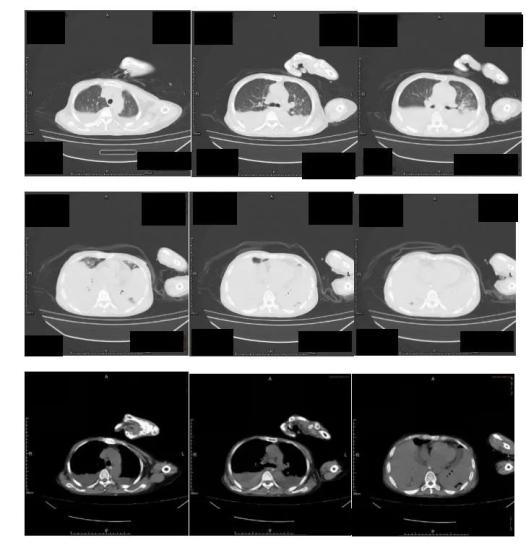

2022年9月14日至我院就诊,查胸部CT(图1):两肺炎症伴实变,两肺多发小结节,拟炎性病变;两侧胸腔积液。纵膈淋巴结增大。心脏增大,心包积液,贫血改变。血气分析(吸氧10L/min):pH 7.51,氧分压 8.68kpa,二氧化碳分压 5.44kpa,标准碳酸氢根 31.1mmol/L、标准剩余碱 7.9mmol/L。

图1 胸部CT(2022.9.14)血常规:WBC 18.89x109/L,N 94.7%,L 3.3%,RBC 2.91x1012/L,Hb 79g/L,PLT 353x109/L,CRP 102mg/L。现患者为求进一步诊治收入我科。

9月21日患者尿液浑浊,絮状物增多,尿培养回报白假丝酵母菌,予以加用大扶康抗真菌治疗;9月23日(图2)复查胸部CT部分较前好转,氧合有好转,吸氧浓度下降至50%左右,低热有反复,咳嗽、咳痰不明显。

图2 胸部CT(2022.9.23)9月25日因痰培养为耐药鲍曼不动杆菌,根据药敏改哌拉西林他唑巴坦为头孢哌酮舒巴坦、米诺环素、多黏菌素抗感染,9月30日因CMV DNA定量>103IU/mL,加用更昔洛韦抗病毒;10月7日因再次发热,痰涂片找到阳性球菌,加用万古霉素抗感染及对症支持治疗。

后患者症状好转,10月8日(图3)复查CT较入院时实变明显有吸收好转,仍有两肺渗出,考虑实变基础上继发感染,但患者无发热,呼吸道症状不明显,鼻导管吸氧,吸氧3L/min呼吸平稳,血象稳定,PCT正常,转至康复医院继续治疗。

图3 胸部CT(2022.10.8)讨论